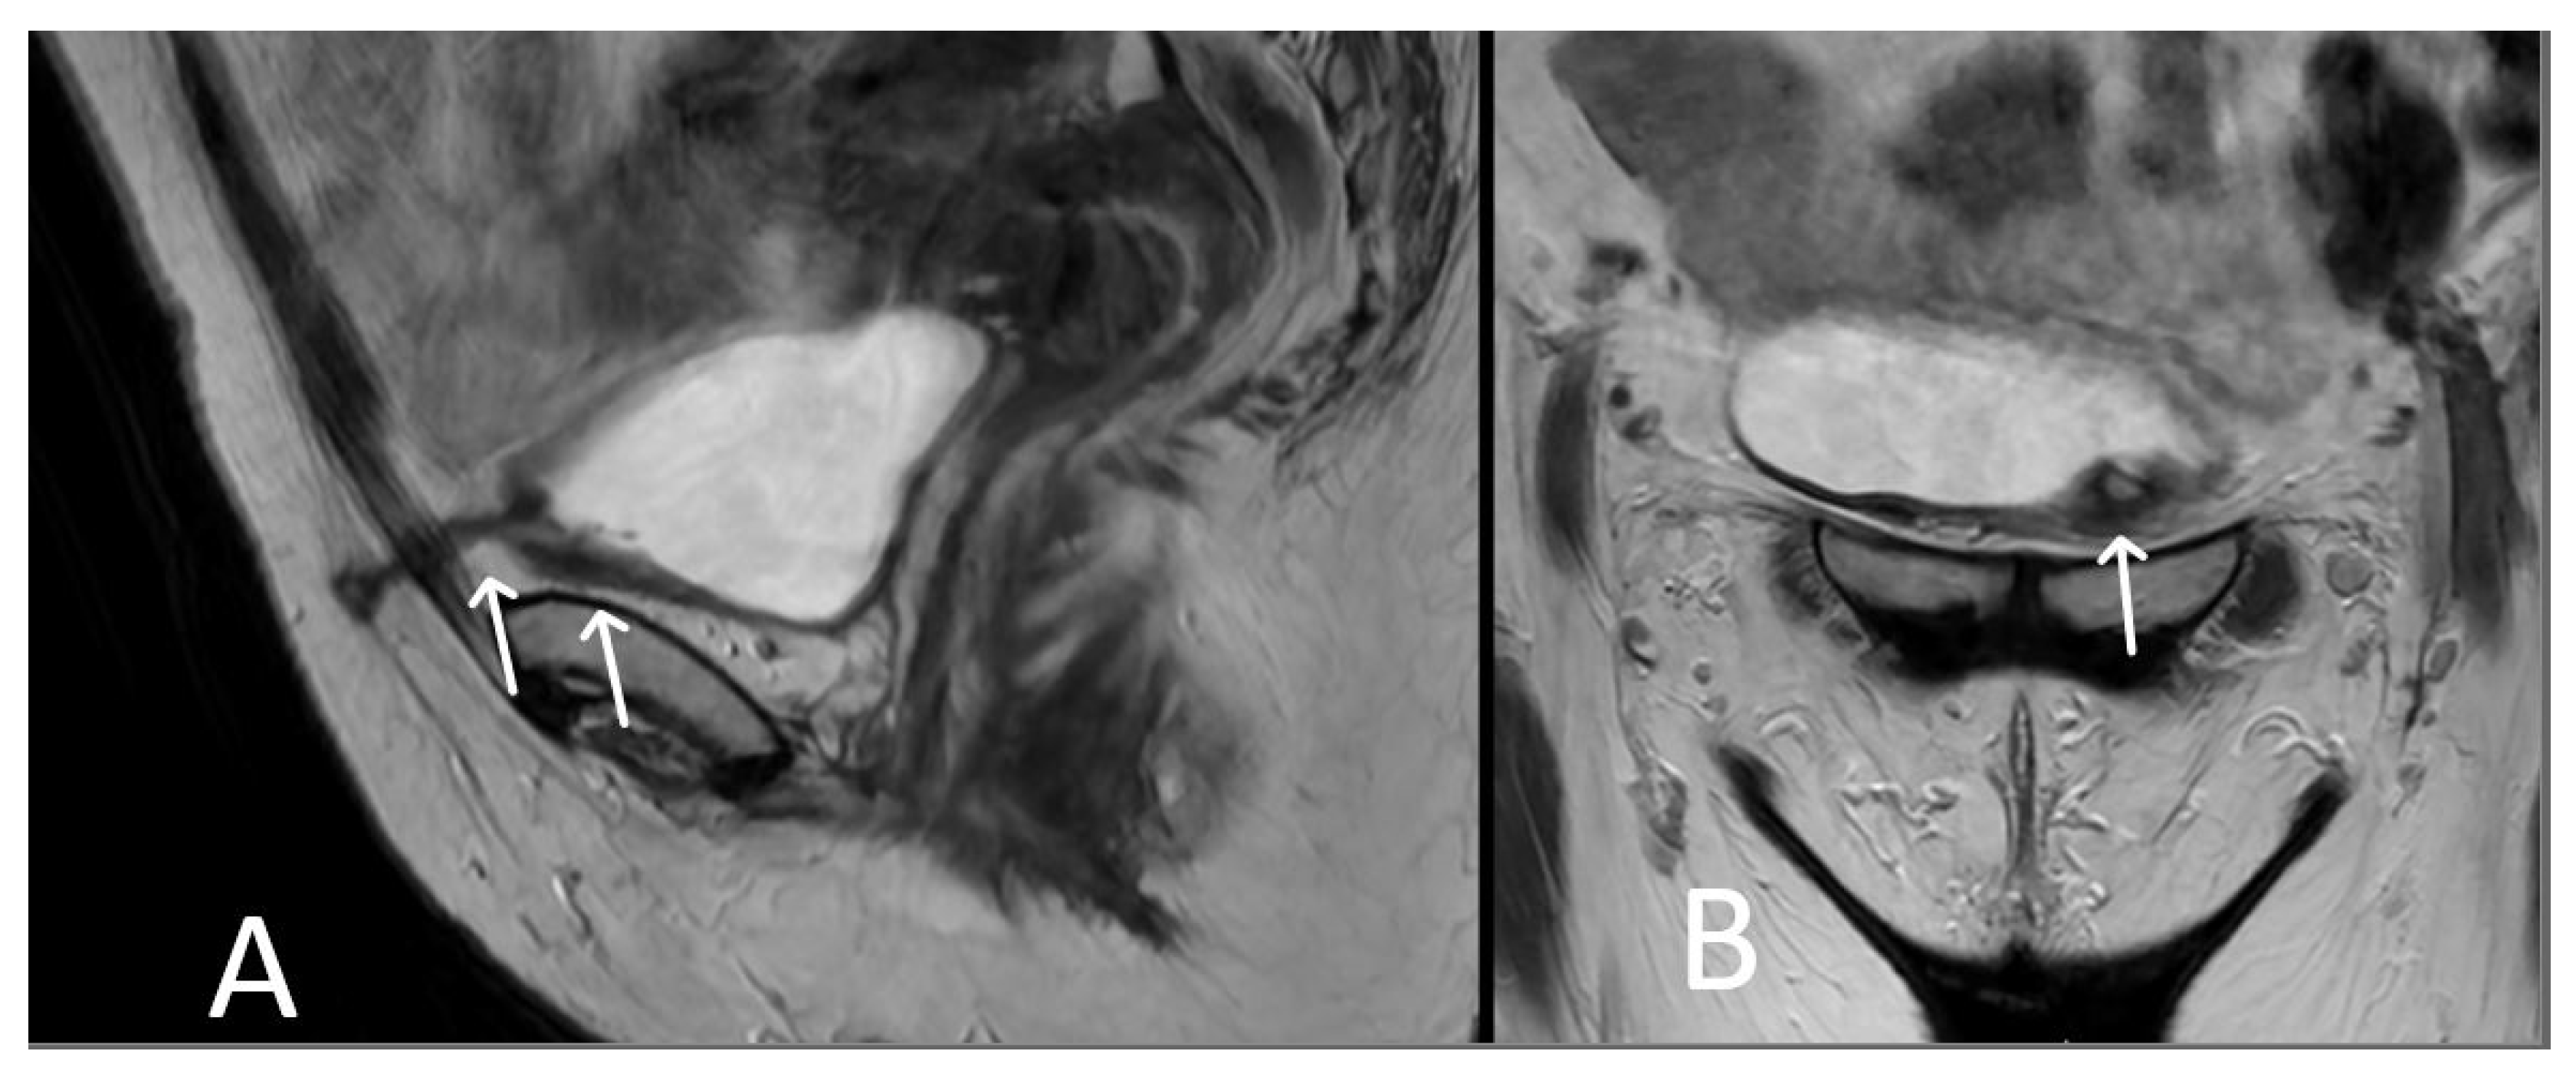

3. Normal Appearance of Urethral Meshes on MRI/CT

4. Urethral Mesh in Oncological Patients